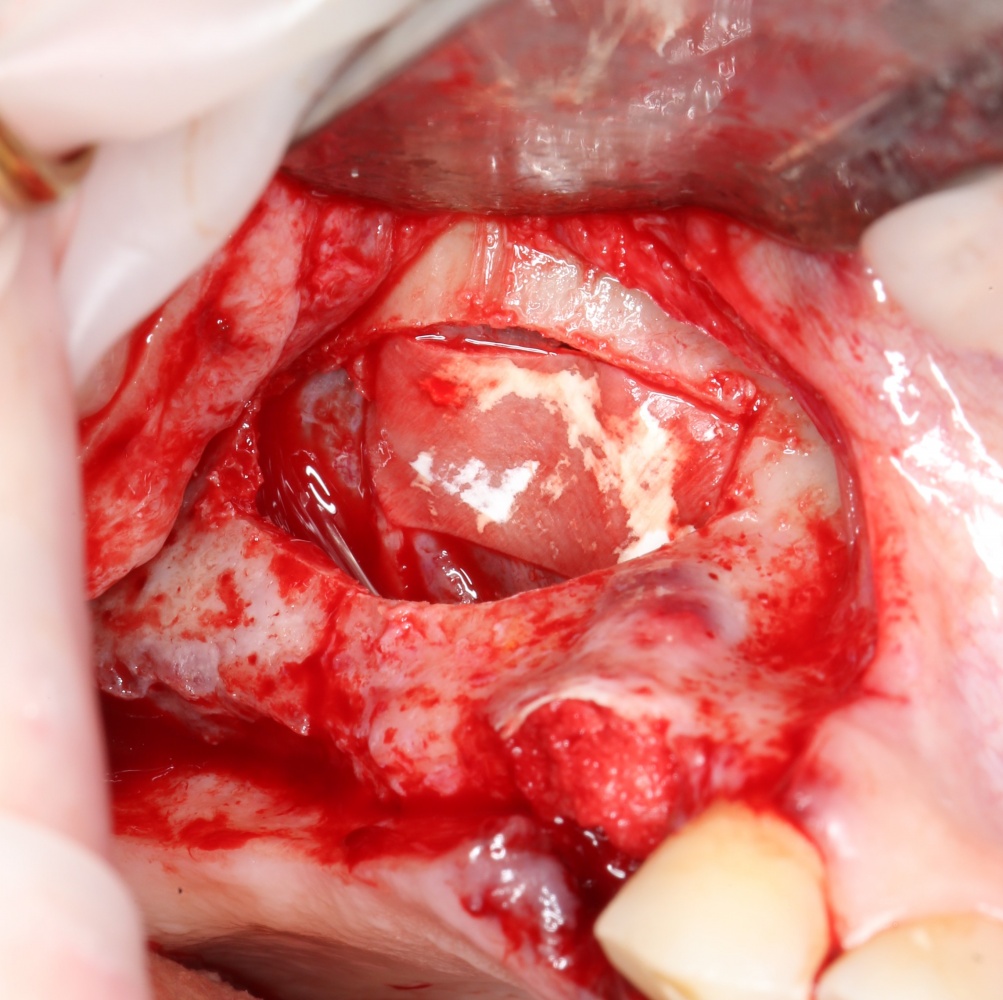

Синуслифтинг: что делать при перфорации слизистой оболочки гайморовой пазухи?